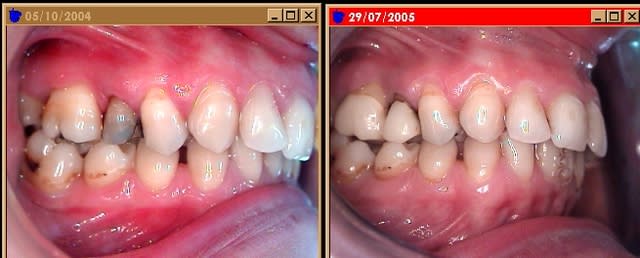

Je remonte ce post de l'oubli pour faire le suivit de cas ( voir premier post, page 1 ).

A noter que l'ODF, finalement, je le fait par activateur SB , donc, pas d'extraction de 15 25 !

Il y a eu tout l'arsenal de la paro med, + laser en juillet., ce n'est pas encore top, mais j'ai bon espoir.

Ce cas remonte à octobre 2004, depuis le microscope m'a permis de voir s'il y avait perte osseuse uniquement sur la 16, je trouvais aussi des maibe au niveau de 26. Donc : traitement complet.